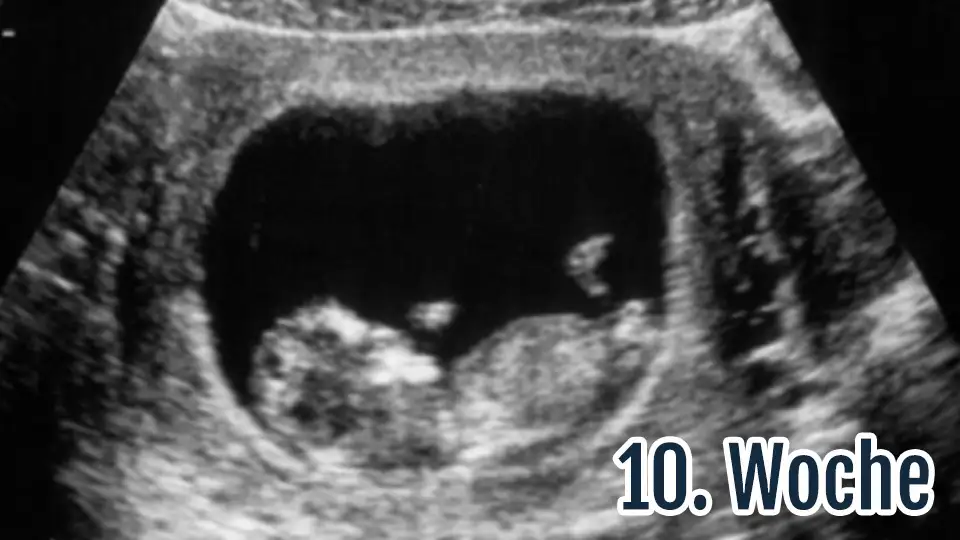

Vay be. Yüz yillardir üst düzey bilim insanlari ve teologlar tarafindan tartisilan bu konuyu, siz catir catir bir cümleyle cözdünüz. Helal sizeYazmayayım diyorum da bilgi sahibi olmadan fikir sahibi olan insanlar ciddi anlamda sinirime dokunuyor. 10 haftalık bir embriyoda beyin, ruh, organ, bilinç hiçbir şey yok. arkadaş cinayet işlemiş olmuyor yani yasal kürtaj yaptırarak. hey allahım.

Rahim gelişimi embriyo ve fetüs olarak gelişim gösterir. Embriyo 10. haftanın sonlarında fetüs olarak görülür ve iç organlar açısından gelişim gösterir. O yüzden zaten 10. haftaya kadar kürtaj yasal olarak kabul edilir.Vay be. Yüz yillardir üst düzey bilim insanlari ve teologlar tarafindan tartisilan bu konuyu, siz catir catir bir cümleyle cözdünüz. Helal size

10 haftalik bir embriyo:

Eki Görüntüle 2298601

Şuan da bilinen anne karnında 4. Hafta da kalbi atmaya başlar. Bundan 30 yıl önce 4 aylıkken falan canlanır diyorlardı. Eminim ki bundan 30 yıl sonra bilim çok daha fazla gelişecek ve döllenme oldugu andan itibaren kalbi atmaya başlar diyeceklerdir . Çünkü Döllenme oldugu andan itibaren büyüyor. Çünkü yaşıyor.Yazmayayım diyorum da bilgi sahibi olmadan fikir sahibi olan insanlar ciddi anlamda sinirime dokunuyor. 10 haftalık bir embriyoda beyin, ruh, organ, bilinç hiçbir şey yok. arkadaş cinayet işlemiş olmuyor yani yasal kürtaj yaptırarak. hey allahım.

Ee yani? Bu kız 30 yıl daha beklesin mi o zaman :d + döllenme olduğu andan itibaren kalp atmaya başlayamaz çünkü ortada bi kalp yok?Şuan da bilinen anne karnında 4. Hafta da kalbi atmaya başlar. Bundan 30 yıl önce 4 aylıkken falan canlanır diyorlardı. Eminim ki bundan 30 yıl sonra bilim çok daha fazla gelişecek ve döllenme oldugu andan itibaren kalbi atmaya başlar diyeceklerdir . Çünkü Döllenme oldugu andan itibaren büyüyor. Çünkü yaşıyor.

Hanımefendi bu mesajınızda 10 haftalık bebekte hiçbir şey yok yazmışsınız. Bunu neye dayanarak yazdınız. şuanda 4. Haftada kalbi atmaya başlandığı bilimsel olarak tespit edilmiş diyorum. siz burada kafadan atmışsınız. Kafanıza göre söylemlerde bulunarak bir bebeğin hayatıyla oynuyorsunuzYazmayayım diyorum da bilgi sahibi olmadan fikir sahibi olan insanlar ciddi anlamda sinirime dokunuyor. 10 haftalık bir embriyoda beyin, ruh, organ, bilinç hiçbir şey yok. arkadaş cinayet işlemiş olmuyor yani yasal kürtaj yaptırarak. hey allahım.